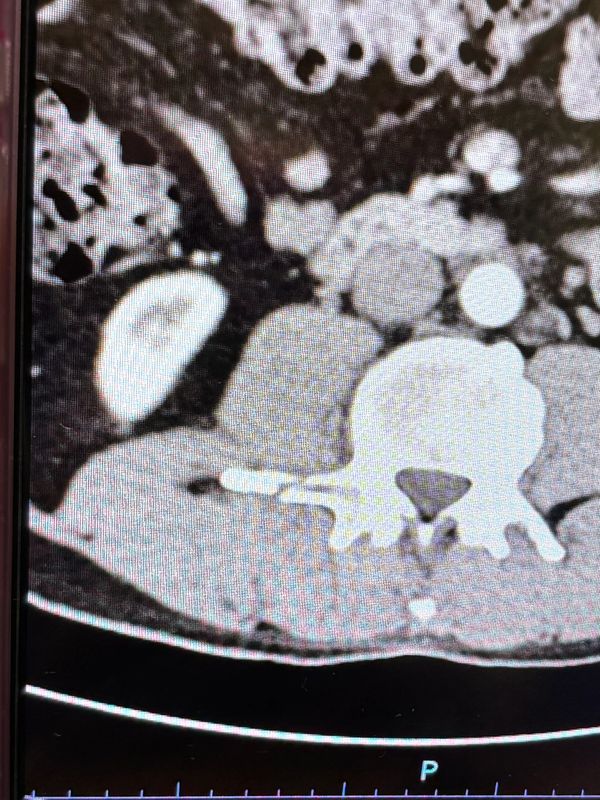

Last Christmas break, in December of 2024, I was surfing in the Galapagos with my family when my dad sustained a L2 to L4 vertebral fracture in the water. International healthcare suddenly became an interest I was passionate about.